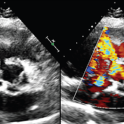

Percutaneous and Non-fluoroscopic Procedure for Atrial Septal Defect Closure, Patent Foramen Ovale Closure and Transcatheter Edge-to-edge Repair

japscjournal.com

Structural heart disease affects patients across all age groups and traditionally requires invasive open-heart surgery or percutaneous interventions with radiation